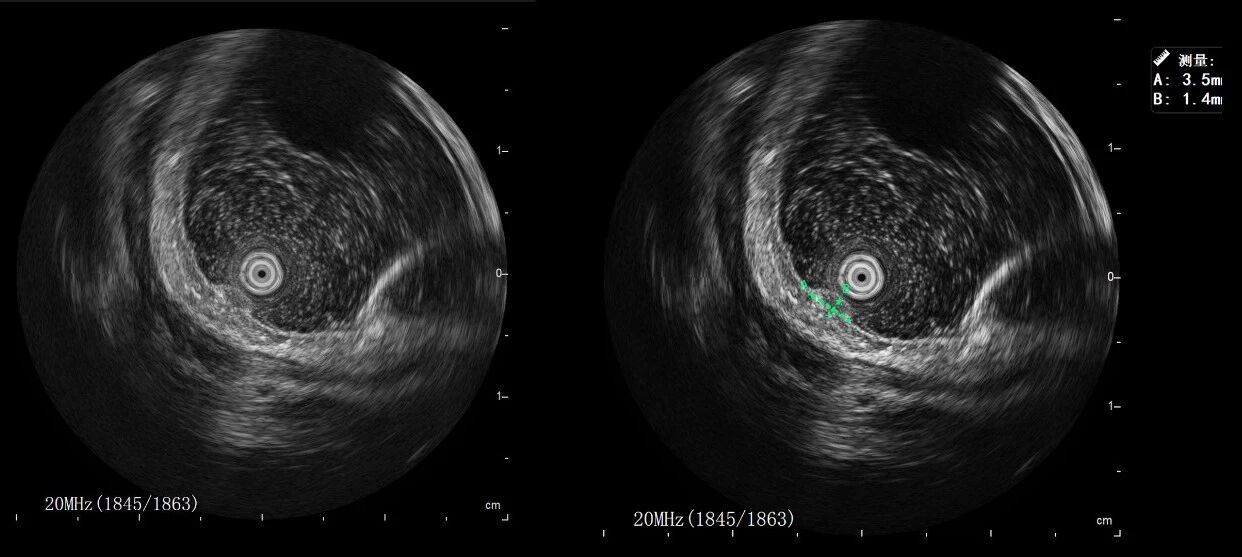

超声内镜:英美达小探头超声内镜 iMP-8902

超声内镜下:直肠可见一大小约3.5mm*1.4mm低回声病变,内部回声均匀,似起源于粘膜层